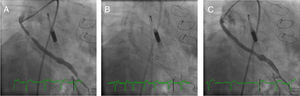

Following local anesthesia, a 6-Fr sheath was inserted into the right femoral artery. After performing a contrast study of the aorta and both iliac arteries, the patient was considered a candidate for using the assist device. A 14-Fr sheath was then placed in the left femoral artery. After administration of 5000 units of unfractionated heparin (UFH), an angiographic pigtail diagnostic catheter (Cardinal Health) was used to deliver a specific 0.14-inch guidewire to the LV. The diagnostic catheter was then removed, and the Impella CP® pump was advanced over the wire across the aortic valve under angiographic guidance (Figure 1A). The pump was started, with a maximum of 3.5 l per minute of circulatory support necessary to maintain the patient hemodynamically stable during the procedure.

Case 1. (A) The right anterior oblique caudal view reveals the saphenous vein graft (SVG) to the first obtuse marginal before intervention and the Impella CP® device. (B) Distal embolic protection device, Emboshield NAV (Abbott Vascular), deployed in the distal portion of the SVG. (C) The right anterior oblique caudal view shows the final angiographic result.

The SVG to the OM1 was intubated with a 6-Fr Amplatz Left 1 catheter (Cardinal Health). A distal embolic protection device, the 6-Fr Emboshield NAV (Abbott Vascular), was gently passed into the SVG across the target lesion and was deployed at the distal portion of the graft (Figure 1B). After pre-dilation of the target lesion with a 3.5×20-mm TREK balloon (Abbott Vascular), a 4.0×28-mm Xience stent was successfully deployed in the SVG. Next, the stent was post-dilated with a 4.5×15-mm Quantum™ Maverick™ balloon (Boston Scientific) at 18 atm. The Emboshield NAV basket was then carefully withdrawn. Aspiration was performed to clear the guide catheter of any debris and thrombi and ensure that none of the contents of the basket remained in the guiding catheter (Figure 1C).